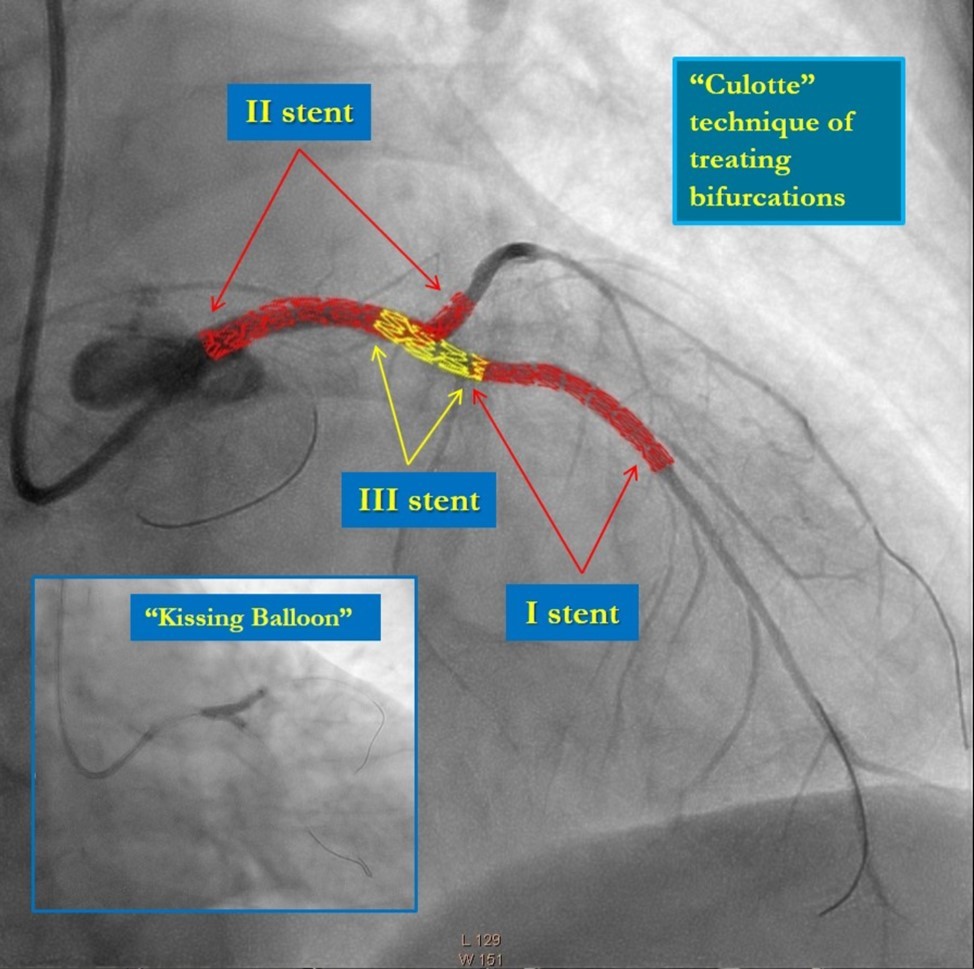

In the first stage, occluded left main and circumflex arteries were recanalized utilizing the support-balloon technique, and CTO wires (Miracle 3™ wire, Abbott Vascular; Runthrough® NS Intermediate wire, Terumo) and balloon pre dilatation was done (Figure 3). In the second stage, the occluded LAD artery was successfully recanalized by utilizing the support-balloon technique, and CTO wires (Figure 3) (due to severe calcinosis the second stage lasted 40 min). In the third stage, LAD artery, CX artery, as well as LMCA and its bifurcation, were stented with 3 drug-eluting stents (Resolute Integrity Zotarolimus DES, Medtronic), the "Culotte Stenting " technique was used for bifurcation stenting (Figure 4), followed by "Kissing Balloon" post-dilatation technique, and finally, proximal optimization technique was performed in the LMCA. The final angiographic image is good, the intervention ended without complications (Figure 5).

Figure 4.Culotte stenting technique

Culotte stenting technique